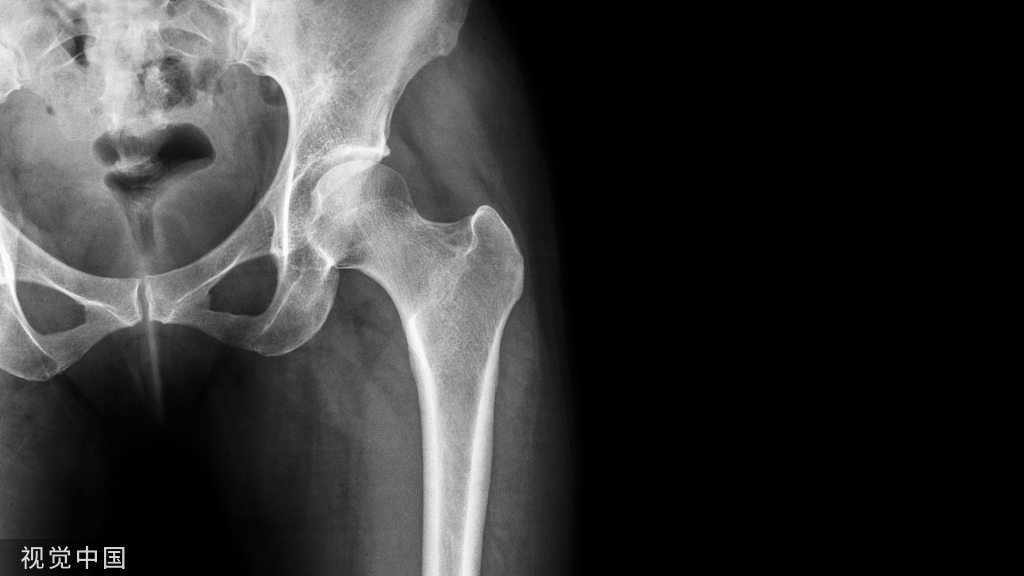

胫骨平台骨折的影像学检查

X线

1、前后位、侧位

2、内旋40度斜位-外侧髁

3、外旋40度斜位-内侧髁

4、牵引位摄片-排除骨片重叠、力线不正

CT

CT三维重建(牵引位)-精确揭示累及关节面的程度范围

26%手术方案的改变(入路、经皮螺钉方向、外固定支架放置)